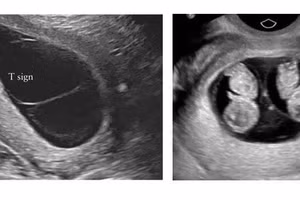

GD&TĐ - Bệnh viện Phụ sản Hà Nội vừa phát hiện một trường hợp thai phụ mang thai song thai cực hiếm, cùng trứng nhưng khác nhau về kiểu hình và kiểu gene.